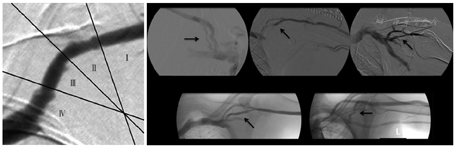

患者女,76岁,因"原发性肾小球肾炎;慢性肾脏病5期"于2011年接受以右颈内静脉临时导管为血管通路的血液透析,同时行右前臂自体动静脉内瘘建立术,术后6周过渡至内瘘穿刺进行血液透析,每周3次。2015年因右前臂内瘘闭塞,行右前臂移植物动静脉内瘘建立术。2016年因右前臂移植物内瘘血栓形成,行右上肢高位内瘘(肱动脉-头静脉内瘘)建立术。2020年3月出现透析中静脉压升高(250 mmHg),拔针后压迫时间延长。查体发现上臂头静脉走行迂曲、打折,伴瘤样扩张,肩部可见头静脉弓走行迂曲。自吻合口起,沿头静脉走行区域均可扪及搏动,伴震颤减弱,头静脉弓区域可触及震颤增强,见图1A。超声二维成像结果显示头静脉弓迂曲狭窄,多普勒血流测定肱动脉血流量1 157.5 ml/min,阻力指数0.54,见图1B。内瘘血管增强CT(三维重建)结果显示内瘘吻合口扩张,上臂头静脉迂曲、打折,伴瘤样扩张,头静脉弓迂曲伴狭窄,见图1C。穿刺内瘘头静脉行头静脉弓+中心静脉血管造影,发现头静脉弓迂曲伴狭窄(70%),中心静脉未见异常,见图1D。行吻合口头静脉缩窄+头静脉弓重建术。手术步骤如下:(1)肘窝处切开皮肤,游离肱动脉、内瘘吻合口及近吻合口头静脉(吻合口旁、瘤样扩张处、打折处)区域,头静脉瘤样扩张处应用6-0 Prolene塑形,近吻合口头静脉应用6-0 Prolene行局部缩窄,长度约1 cm,切除局部多余皮肤后,缝合皮肤;(2)锁骨下中外1/3处切开皮肤,游离头静脉弓区域,切除狭窄迂曲部分,两残端用7-0 Prolene行端端吻合,局部止血后缝合皮肤,见图2。术后查体上臂头静脉血管张力较术前明显降低,透析穿刺顺利,透析中静脉压明显下降(180 mmHg)。术后1个月后随访,彩色多普勒超声检查示肱动脉血流量1 088.0 ml/min,阻力指数0.45。术后3个月后随访,肱动脉血流量927.4 ml/min,阻力指数0.46。

注:A:吻合口增大,近吻合口头静脉瘤样扩张;B:缩窄吻合口,瘤体塑形,切除打折狭窄段后端端吻合;C:头静脉弓迂曲、狭窄;D:切除头静脉弓迂曲狭窄后行端端吻合;E:缝合皮肤

肘部高位内瘘(肱动脉-头静脉内瘘)导致CAS发病率并不低,最早由Glanz等[4]于1982年提出。与RCF相比,肱动脉-头静脉内瘘发生率显著较高,其原因与肱动脉-头静脉内瘘高血流量及头静脉弓作为单一的内瘘静脉流出道有关[5]。CAS的病理生理机制包括:(1)内瘘建立后的血流动力学变化;(2)锁胸筋膜和胸大肌的外在压迫阻止了头静脉扩张以应对增加的剪切力;(3)头静脉弓自身的形态;(4)静脉瓣膜增多及肾衰竭引起的血管改变[6,7,8]。为了将CAS标准化及进行准确、可重复性测量,Bennett等[9]提出将头静脉弓分为Ⅰ、Ⅱ、Ⅲ、Ⅳ共4段,发现CAS最常发生在足弓的末端,与Ⅰ、Ⅱ区相比,Ⅳ区最易发生狭窄。头静脉弓为浅静脉,存在一定变异,最常见的是与腋静脉连接形成锁骨下静脉的单一通道,有时候会遇到双弓。双弓呈分叉状,两分支可同时汇入腋静脉,或1支汇入腋静脉,另1支与颈内静脉或颈外静脉相连。头静脉弓也可以直接汇入颈外静脉、颈内静脉或锁骨下静脉[10]。见图3。